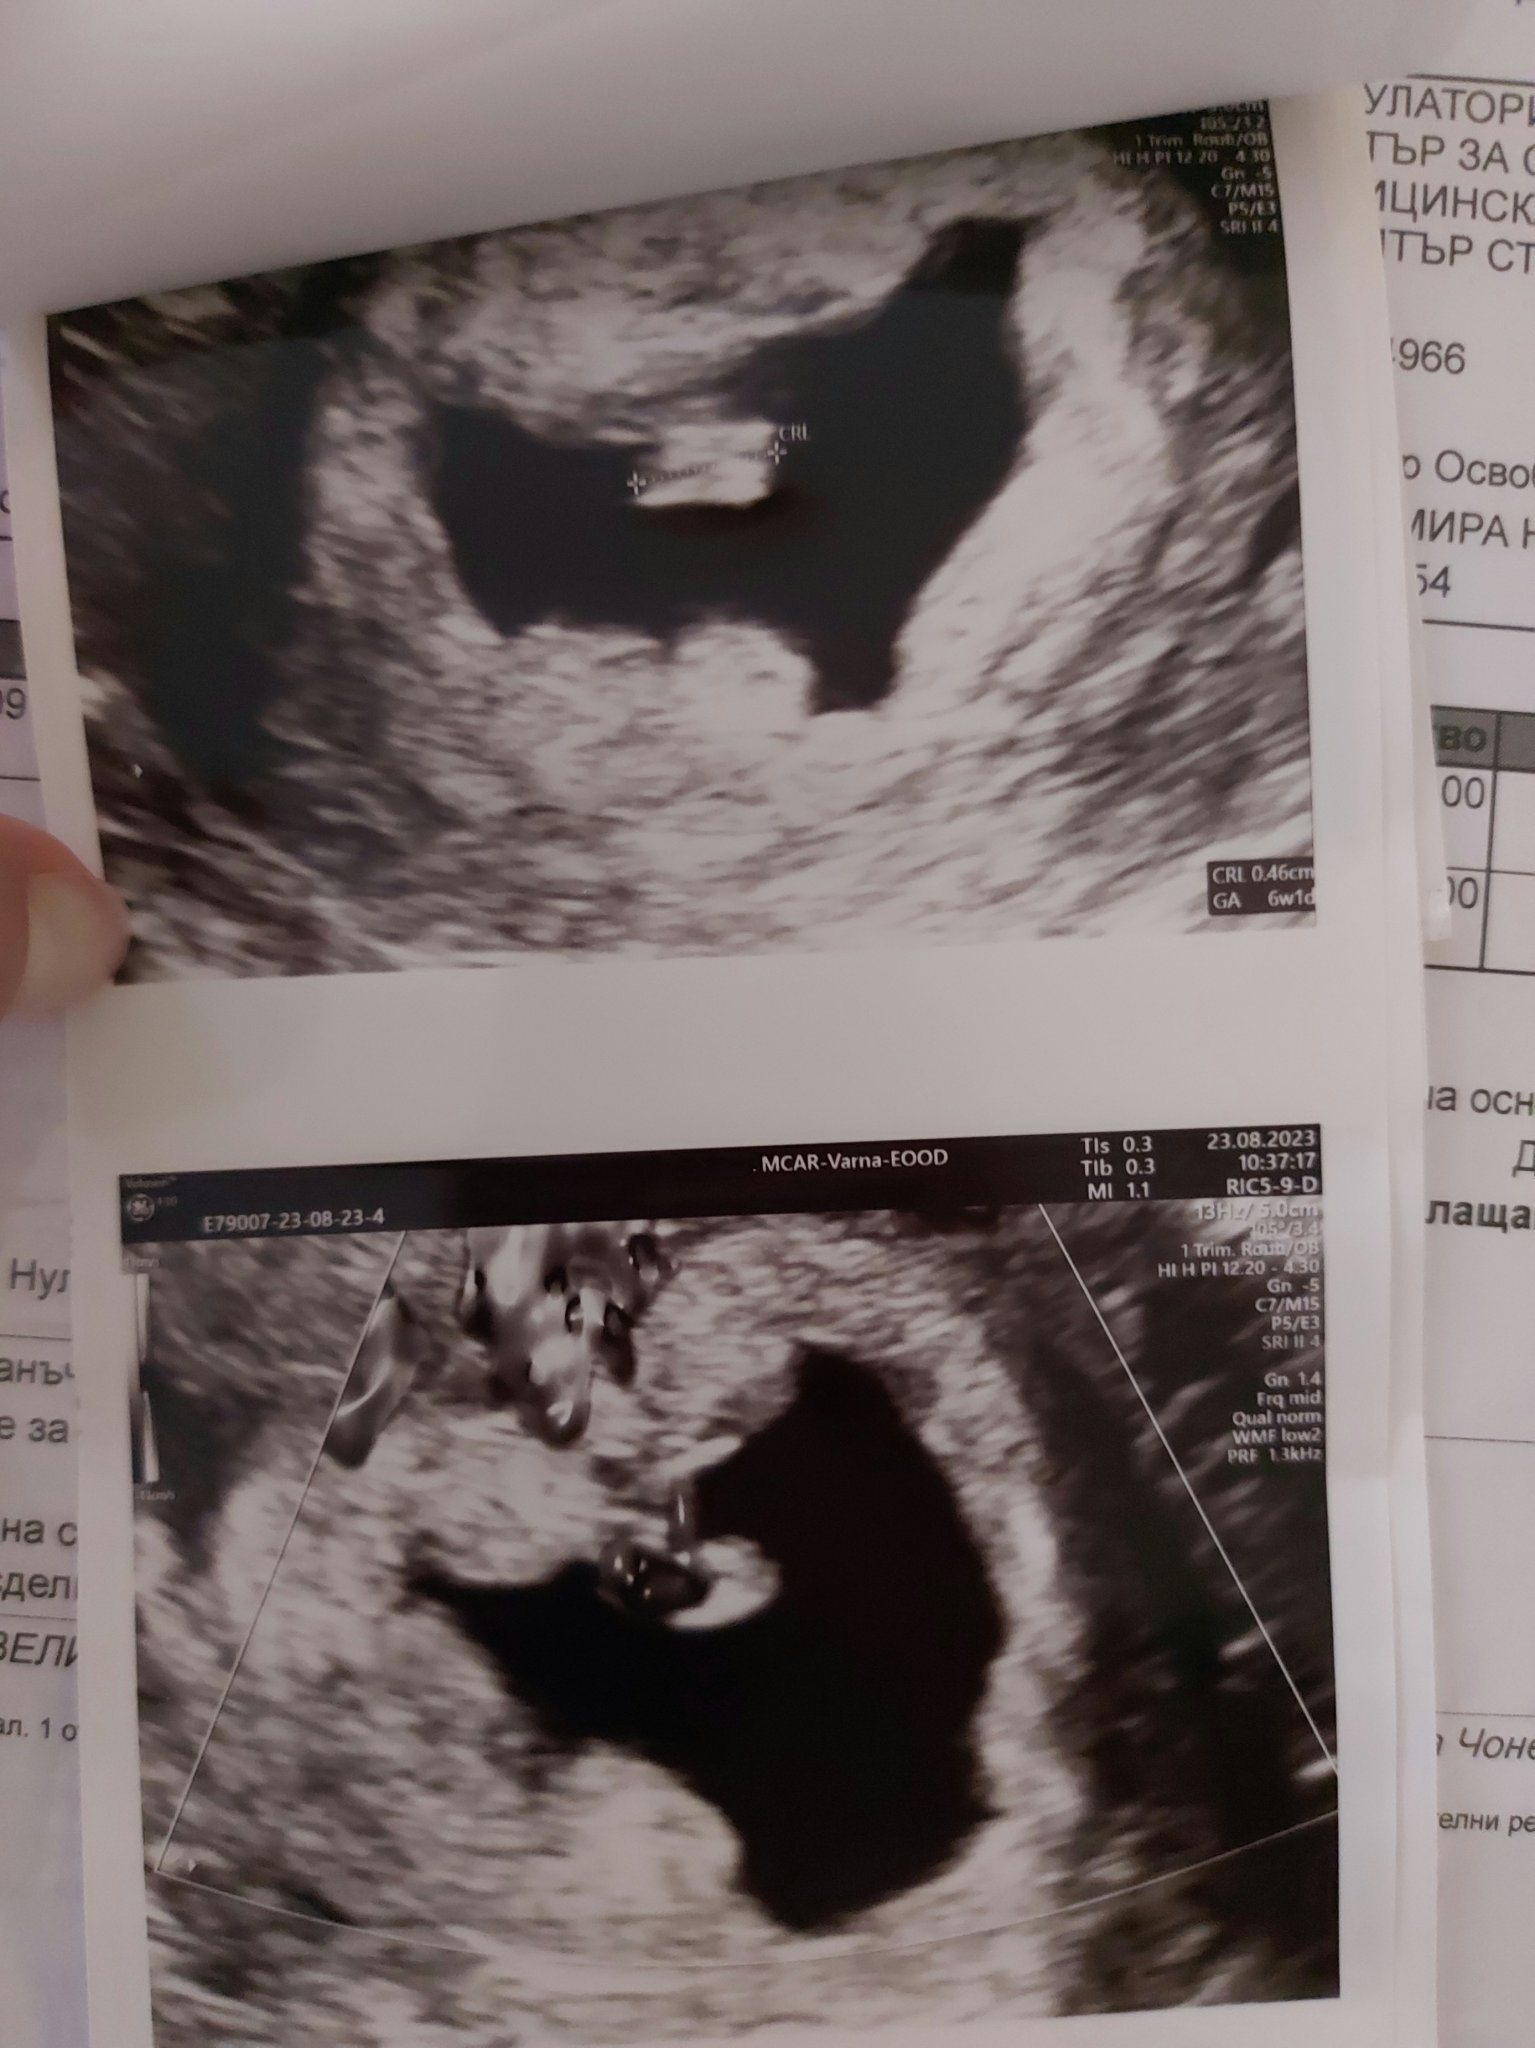

Прикачвам ви снимка на сака да го видите, наистина не беше нормално